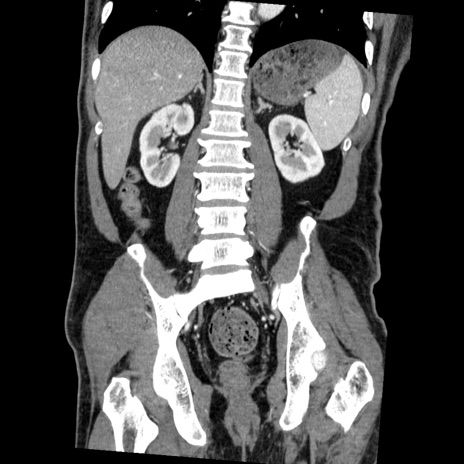

症例22(冠状断像)

【症例】50歳代男性

【主訴】腹痛

【現病歴】AVMからの被殻出血のため回復期リハ病棟入院中。 本日午後3時頃急に下腹部痛が出現した。

【既往歴】AVM、被殻出血、虫垂炎、高血圧

【身体所見】意識晴明、左半身不全麻痺、会話の理解は良好、36.5°C、腹部:膨隆、全体に板状硬、下腹部正中に圧痛点あり、反跳痛-、筋性防御不明、右下腹部にope scar

【データ】WBC 9400、CRP 0.06